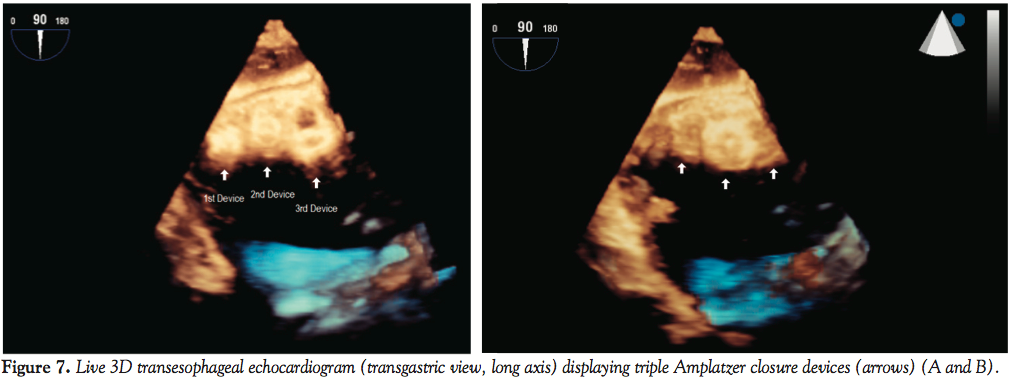

On postoperative day 1, the patient remained hemodynamically stable, and TTE revealed no change in residual VSD with well seated Amplatzer occluders absent of any rocking motion abnormalities; inferior left ventricular wall aneurysm was unchanged. On the second postoperative day, the patient was extubated and intra-aortic balloon pump was removed. The patient was discharged on postoperative day 8. At 30-day follow-up, the patient was clinically stable with no deterioration in status. However, approximately 8 weeks post-discharge, the patient presented to our facility with chief complaint of severe shortness of breath and evidence of congestive heart failure; TTE revealed recurrent VSD shunt (Figure 6). He was again deemed to be high-risk for surgical repair of VSD. The patient was readmitted and brought to the interventional cardiology suite for further evaluation. Under general anesthesia, TEE confirmed the presence of residual VSD with shunt at the basal septal wall. A 12 mm VSD Amplatzer occluder device was deployed across the VSD in the standard technique under fluoroscopic and echocardiographic guidance through a 9 Fr x 180 cm TorqVue delivery system placed in right internal jugular vein. Post-deployment, the third device was noted to have diminished the VSD. All 3 Amplatzer occluder devices were aligned parallel to one another (Figures 7A and 7B).

At 9-week follow-up, TTE was performed and findings included: 1) left ventricular ejection fraction of 62%; 2) appearance of 3 Amplatzer devices along the interventricular septum seated well with no motion and residual shunt; 3) moderate diastolic dysfunction with pseudonormal left ventricular filling pattern; and 4) no valvular abnormalities. The patient had increased exercise tolerance with no shortness of breath at rest or with exertion.